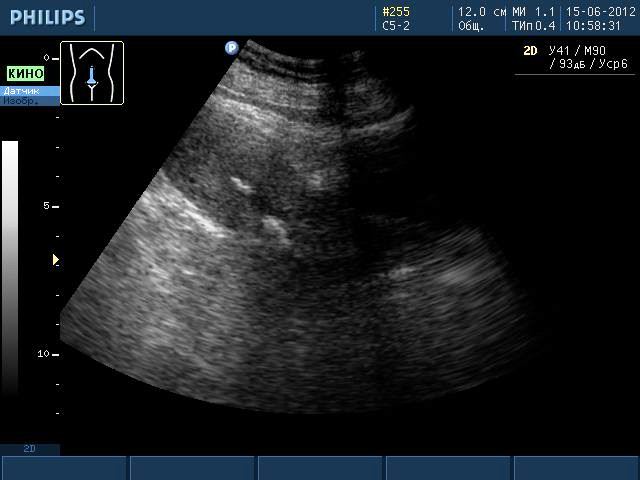

Такие образования хорошо видны при ультразвуковом исследовании, МРТ. Но во время УЗИ не видны ткани, из которых состоит образование, поэтому о наличии кальцината можно только предположить. Такая ситуация требует дополнительного обследования женщины, чтобы исключить заболевания гораздо серьезнее, чем наличие отложений солей кальция.

Кальцинат на УЗИ

Распространенным методом диагностики является ультразвуковое исследование детородного органа. Гинекологи предлагают трансабдоминальное УЗИ, которое позволяет исследовать патологии органа с помощью датчиков, которые врач водит по животу пациентки.

- трехмерное УЗИ – современный способ диагностики патологий матки, который позволяет в трехмерном измерении увидеть кальцинаты;

Трехмерное УЗИ на сегодняшний день является самым достоверным способом диагностики заболеваний матки, но его цена значительно выше остальных методов.